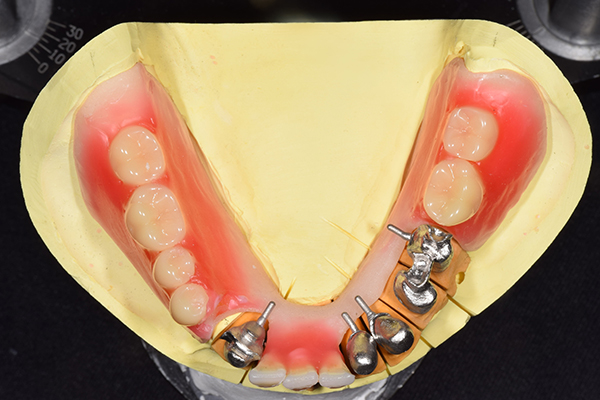

ケース4

(アタッチメントを用いた部分入れ歯)

右上のインプラント周囲炎で、その部分が痛いという患者様でした。 また奥歯で噛むことが難しかったため、前歯を使用することが多くなり、 前歯が前よりも前に出てきていることも気になっていらっしゃいました。

インプラント部以外にも歯周病が進行していましたので、歯周病の治療を行いました。 残念ながらインプラントと、1本の歯が残せなかったため抜歯を行いました。 その後、前歯の出っ張りを修正することと入れ歯の安定を図るため、残っている歯を全てかぶせ物にしていくことになりました。 写真中央は抜歯後に入れた治療用の入れ歯になります。 抜歯後歯ぐきが安定しましたら、入れ歯とかぶせ物の型取りを行いました。

噛み合わせチェックでしっかり奥歯で噛めるようにし、 歯を並べます。 その後、それに合わせて前歯を作っていきます。

最終的な入れ歯用の型取りをします。 シリコンで精密に型取りができました。

こちらが完成したかぶせ物と入れ歯です。かぶせ物にはアタッチメントをつけて金属のバネが見えない構造になっています。 入れ歯自体も金属を使用して、極力違和感がでないように、薄く作成しました。

お口の中に入れた状態です。 非常に見た目もよい出来となりました。 バネがみえないと見栄えが全然ちがいます。

年齢 70代・女性

主訴 奥歯のインプラントが痛い。

前歯がでてきた。

治療期間 6ヶ月

治療費 .メタルボンドクラウン7本:770,000円

.アタッチメント2個:220,000円

.義歯:550,000円

治療方針 ゆれてきたインプラントを抜去した後、歯周病の治療と、予後不良の歯を抜歯して、義歯を作成します。

抜歯後は治療用の入れ歯を作成し、ものが噛める様にします。

また前歯は、被せものをすることにしました。

治療内容 右上のボーンアンカードブリッジ(インプラントのブリッジ)部分がインプラント周囲炎になり、ぐらぐら揺れてきました。

そのため、インプラントを抜去した後、歯周病の治療と、予後不良の歯を抜歯して、義歯を作成していきました。

見た目が入れ歯とわからない様に針金のない、アタッチメントを使用した入れ歯を作成することにしました。

抜歯後は奥歯でものが噛める様に治療用の入れ歯を作成しました。

また前歯はフレアアウト(奥歯で噛めなくて前歯で噛む様になって、前歯が前に出てくる現象)していたため、患者さんの希望でかぶせ物をすることにしました。

特記事項 歯やインプラントを抜いた後は、2〜3ヶ月歯ぐきの回復を待ってから入れ歯を作るため、待機期間があります。その間、治療用の入れ歯を調整しながら使います。かぶせものをした後は歯がしみたり、場合によっては神経を抜く処置が必要になることもあります。